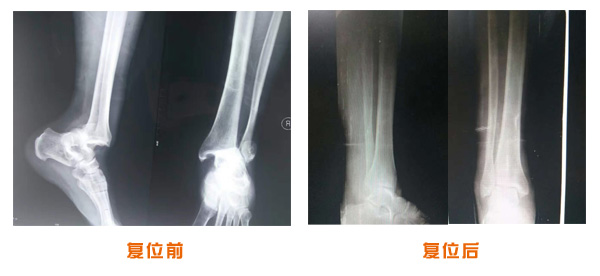

復位前后對比

肘關節脫位骨折治療前后對比

踝關節脫位骨折治療前后對比